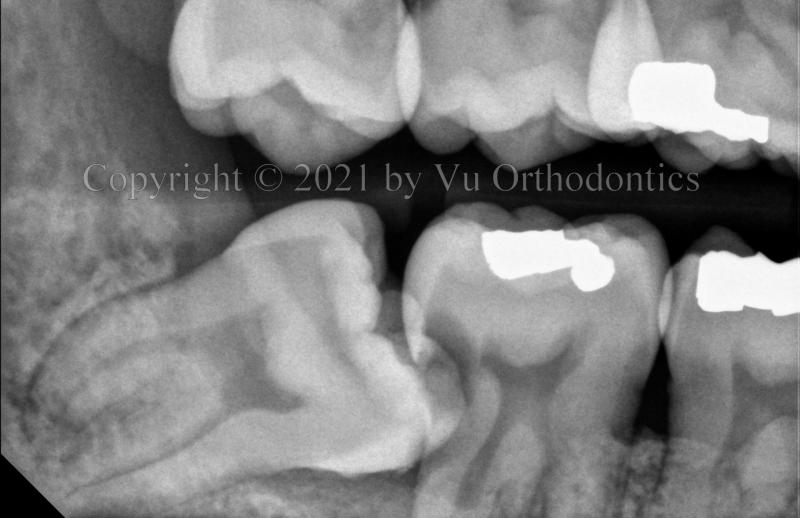

Figure 2 shows the result of impacted wisdom tooth #17 corrected after orthodontic treatment.

Fig. 2 Wisdom tooth #17 corrected by orthodontics (near the end of the treatment)